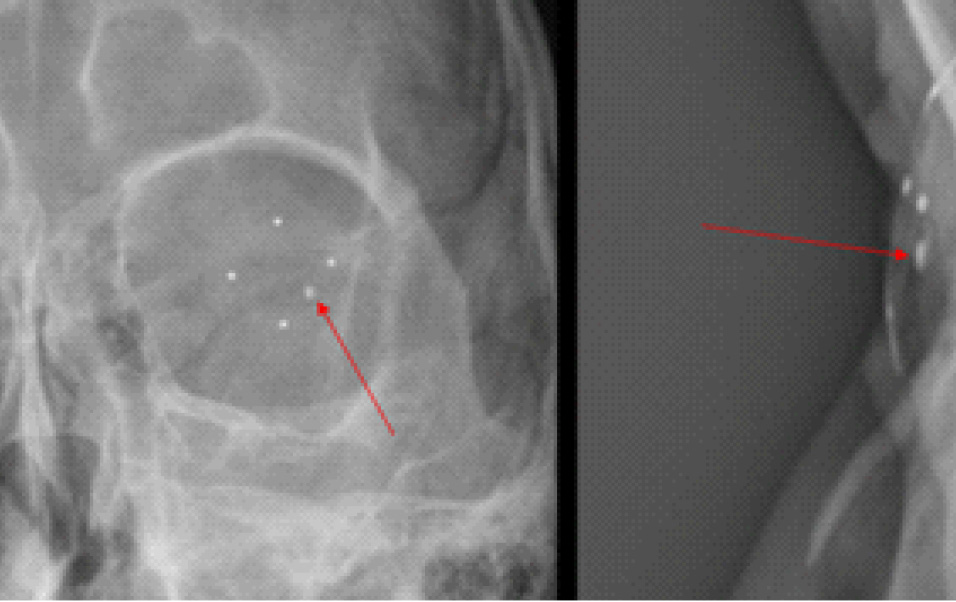

Пациенту был проведен комплекс инструментальных исследований, включающий в себя ультразвуковое исследование (УЗИ) и ультразвуковую биомикроскопию (УБМ), рентгенографию глазниц (РГ) с локализацией инородного тела по методу Комберга – Балтина, компьютерную томографию (КТ) головы. Эхографическая картина заднего сегмента OS имела следующие особенности: витреоретинальные тяжи, мелкодисперсная взвесь – выпот, хрусталик люксирован в стекловидное тело, нельзя исключить ВГИТ на глазном дне. УБМ выявила инородное тело в передней камере по меридиану 4–5 часов (рис. 2). При рентгенографии OS по Комбергу – Балтину определялось ВГИТ размерами 2 × 1 × 1 мм, по меридианам 4 часа 10 минут – 4 часа 40 минут, на расстоянии 4 мм от анатомической оси глаза, на расстоянии 1–2 мм от плоскости лимба (3–4 мм при пересчете на склеру) (рис. 3).

Рис. 2. УЗИ и УБМ левого глаза

Рис. 3. Рентгенография по методу Комберга – Балтина. ВГИТ указано стрелкой